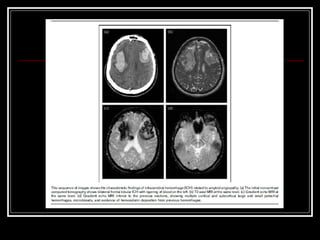

Diagnóstico TC de crânio sem contraste na fase aguda do evento  Limitações: Infratentorial tronco Outros: Lobar? Idade < 45 anos?Hemoventrículo solitário?Sem HAS? RNM e suas variações, arteriografia, etc. para investigação da etiologia do sangramento HDA e HPP (trauma? Anticoagulação? Drogas? Dça hematológica)

Hemorragia Intracraniana: Imagem Tomografia computadorizada vs. Ressonância Magnética de crânio Angiografia HSA; Calcificações anormais; malformação vascular óbvia; sangramento em topografia incomum (p.ex. fissura silviana); pacientes sem causa óbvia de sangramento (p.ex. hemoventrículo isolado) Hemorragia lobar Hemoventrículo isolado HSA associada Sangramentos recorrentes Pacientes sem histórico de HAS Pacientes com 45 ou menos anos Causa primária desconhecida e que serão submetidos a cirurgia E se ainda assim após arteriografia normal houver a suspeita de hemorragia secundária? Repetir arteriografia com 2-4 semanas após resolução do hematoma

Diagnóstico TC decrânio sem contraste na fase aguda do evento Limitações: Infratentorial tronco Outros: Lobar? Idade < 45 anos?Hemoventrículo solitário?Sem HAS? RNM e suas variações, arteriografia, etc. para investigação da etiologia do sangramento HDA e HPP (trauma? Anticoagulação? Drogas? Dça hematológica)

Hemorragia Intracraniana: ImagemTomografia computadorizada vs. Ressonância Magnética de crânio Angiografia HSA; Calcificações anormais; malformação vascular óbvia; sangramento em topografia incomum (p.ex. fissura silviana); pacientes sem causa óbvia de sangramento (p.ex. hemoventrículo isolado) Hemorragia lobar Hemoventrículo isolado HSA associada Sangramentos recorrentes Pacientes sem histórico de HAS Pacientes com 45 ou menos anos Causa primária desconhecida e que serão submetidos a cirurgia E se ainda assim após arteriografia normal houver a suspeita de hemorragia secundária? Repetir arteriografia com 2-4 semanas após resolução do hematoma